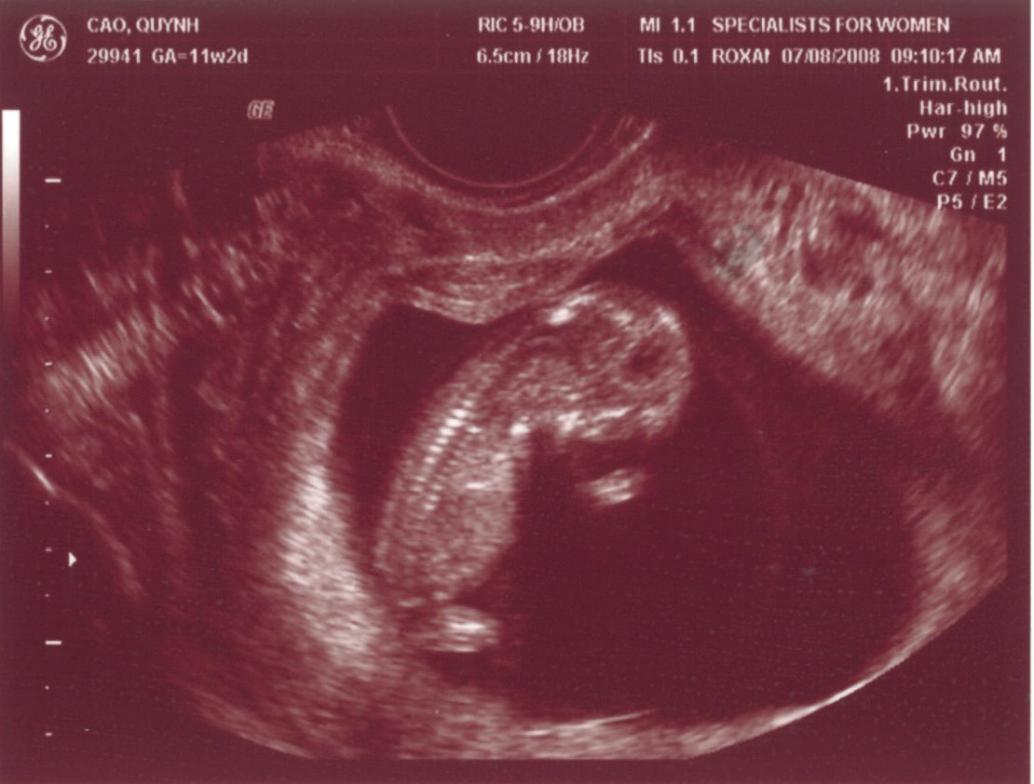

Ngày 11/28/1999 Ba Mẹ có nhau, lúc đó con ở đâu ha? Ngày 5/27/2008, con đây rồi!!! Mới được 2 tuần, là hạt nhân nhỏ xíu trong bụng Mẹ thôi Ngày 6/4/08, lần đầu tiên Ba Mẹ nghe tim con đập, 124 nhịp/phút. Mẹ sung sướng nhìn con. Còn Ba thì rơm rớm nước mắt, hihi!! Ngày 7/8/2008, con được 11 tuần rồi, bắt đầu có tay chân rồi đây... 1 tuần sau tay chân con đã dài ra rồi, lẹ ghê... ...biết nhào lộn vòng vòng nữa, mới nằm úp giờ nằm ngửa rồi. Ngày 9/3/2008, Mẹ chưa muốn biết con là trai hay gái vì muốn bất ngờ, nhưng rồi cuối cùng cũng không đợi được... ...hihi, cục cưng của Ba Mẹ là con trai. Con trai miệng bự giống Ba.  19 tuần là mắt mũi miệng đầy đủ hén. Từ khi biết có con, Mẹ nhờ Ba chụp hình hai mẹ con mình. Cái này là lúc con được 2 tháng trong bụng Mẹ.. ...24 tuần, con bắt đầu cựa quậy lung tung mỗi ngày... ...36 tuần, có lúc Ba Mẹ tưởng đã mất con nhưng con vẫn lớn giỏi ngoan... ..39 tuần, con nặng quá rồi nhưng Mẹ vẫn muốn con ở trong đó thêm chút nữa cho lớn lớn... Ba thì nôn gặp con quá, ngày nào Ba cũng nói chuyện với con.  Bụng Ba cũng bự rồi nè! Ngày 1/20/2009, con 39 tuần, bác sĩ muốn con ra sớm cho an toàn.  Ba Mẹ hồi hộp đợi tới lúc gặp con... Sau gần 8 tiếng chờ đợi thì con ra đời!! Con mở mắt nhìn Mẹ như là biết rồi đó.  Thương con ghê nơi! 1 tuần tuổi thì rụng rún.  2 tuần tuổi thì chụp hình lần đầu với Mẹ, nhỏ xíu xiu xiu... 7 tháng (8/2009) con bò lung tung, chụp hình mà không yên... 14 tháng (4/2010) con chỉ muốn chạy chơi thôi, Ba chụp lẹ lẹ nghe. Ngày 2/19/2010 Ba Mẹ làm lễ cưới ở nhà thờ.  Lần này thì có con rồi.  Có con Ba Mẹ có tất cả...